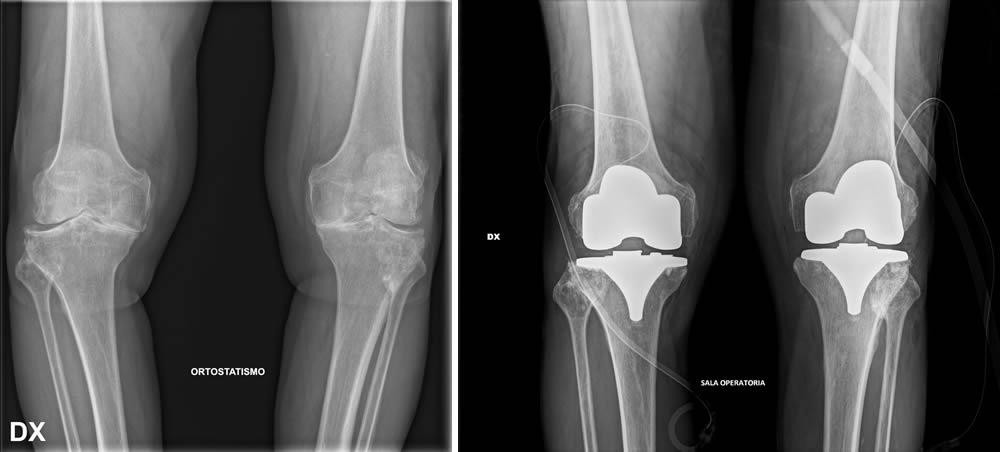

Prima e dopo l'intervento

Per formulare una diagnosi corretta e ottenere un quadro clinico completo del paziente, è fondamentale eseguire una radiografia (RX) del bacino o bilaterale ginocchio in carico ovvero in piedi.

Quando si prende in considerazione la protesi al ginocchio, si aprono diverse possibilità di intervento. È possibile optare per soluzioni mini-invasive che prevedono l'inserimento di protesi monocompartimentali, adatte a sostituire solo una parte dell'articolazione, oppure per protesi parziali o totali, in base alle esigenze e alla gravità della situazione. La scelta dell’intervento viene valutata attentamente dal chirurgo, mirando sempre a garantire il miglior recupero funzionale possibile.